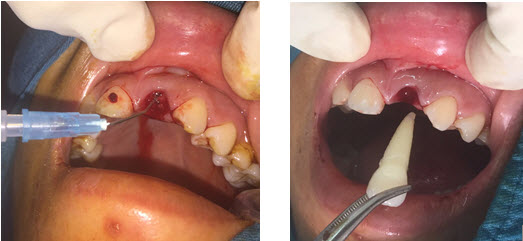

V. Một số hình ảnh

2020 04 15 9 20 36

2020 04 15 9 21 56

image 20200415091711 6

3. Cấy răng trở lại vị trí ban đầu

Dùng dụng cụ thích hợp lấy răng bị bật nhổ ra khỏi dung dịch nuôi dưỡng và đặt vào huyệt ổ răng theo giải phẫu ban đầu.

Kiểm tra khớp cắn, đảm bảo răng không chạm mặt phẳng cắn.

Cố định răng.

Sau khi xử lý ổ răng, đặt răng vào ổ răng rồi cố định ngay càng sớm càng tốt. Tùy điều kiện có thể sử dụng phương pháp cố định nẹp hay composite vào các răng lân cận. Thời gian cố định từ 10 – 14 ngày. Có thể chụp phim để xác định răng đã đúng vị trí hay chưa trước khi cố định. Cố định bằng chỉ thép có ưu điểm điểm vững hơn cố định bằng composite, tuy nhiên khó vệ sinh răng miệng và đôi khi tạo thành túi nha chu. Ngoài ra cần lưu ý khi cố định bằng chỉ thép phải buộc trên cingulum để tránh tình trạng gây trồi răng.